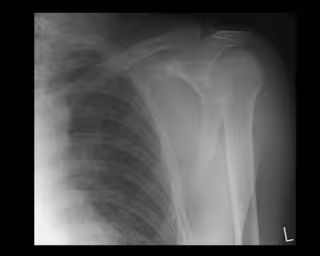

Las nuevas prótesis de hombro permiten que el paciente pueda volver a mover el hombro sin dolores

Hombro